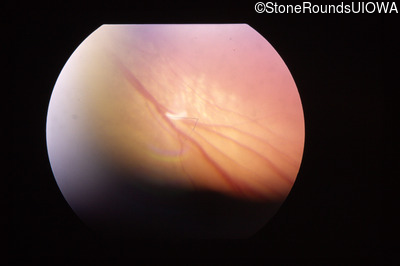

Visit at age: 4 years

Fundus Photography - Left - Count Fingers 5'

Exemplar